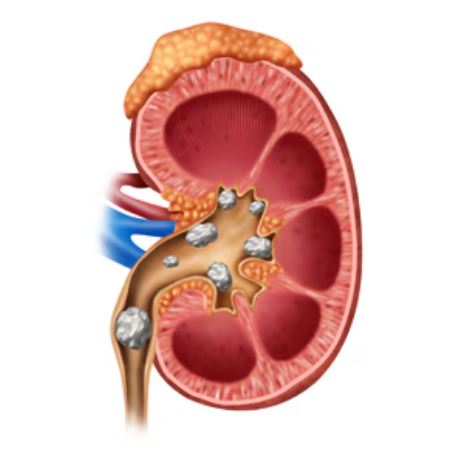

Minimally Invasive Kidney Stone Treatment in Thane...

thane clinic maintained reach effective procedures urology clinic reduced discomfort youre dealing kidney health remove stones kidney stones opting longterm prevention ensuring personalized care plans daily lives sooner helps patients return major surgical interventions ensure faster recovery minimally invasive treatment